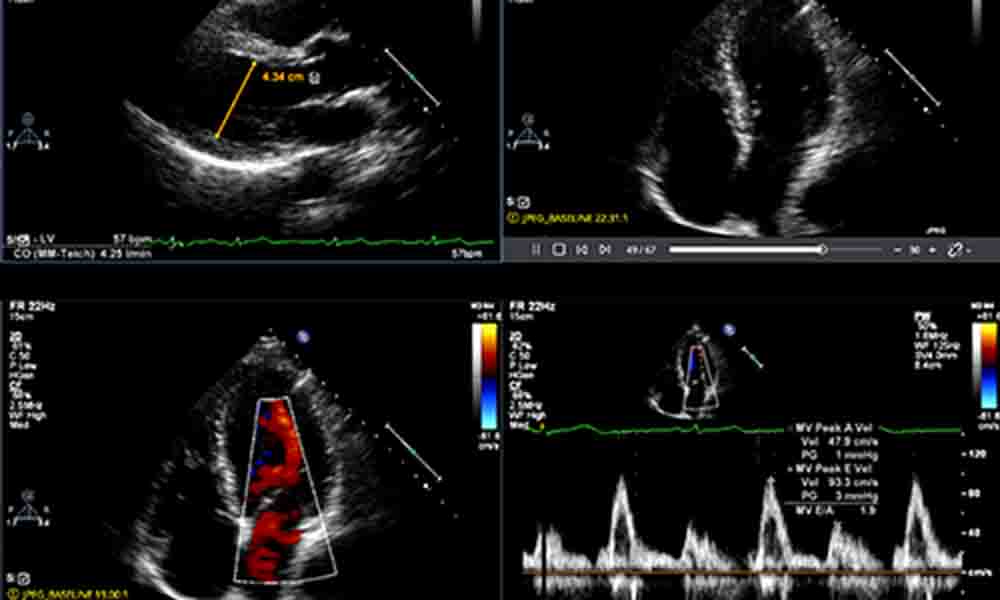

Echocardiography

EncaptureMD is the fastest way to create adult echocardiogram reports. EncaptureMD’s Echo point and click interface eliminates dictation, is standards-compliant, IAC-ready and accelerates documentation, improves accuracy and adapts to your work flow. Measurements flow directly in from the modality and begin to build the report. AI integration automates measurement and diagnosis. Treadmill system integration provides waveform and exercise information allowing a single stress echo report.